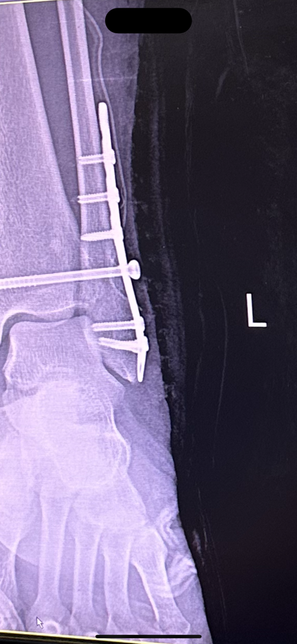

- 의료법률노련한참밀드리138골절 수술 후 체내 쇳조각이 살을 뚫고 나옴12/11 발목 골절 수술(심 박는) 받았습니다 수술 진행 후 엑스레이도 찍고 무사히 잘끝났다는 말에 안심하고 시간을 보낼 수 있었습니다 그리고 일주일간 입원 후 퇴원한 뒤 수술한지 2주가 지난 시점 지금까지 감고 있던 붕대를 풀고 집으로 돌아간 뒤 확인해보니 저렇게 낚시바늘같은것이 살을 뚫고 나와있었습니다당장 주말과 크리스마스연휴라 내원을 하지 못하고 몇일이 지나 내원을 했더니 이런 쇳조각이 몸안에서부터 살을 뚫고 나왔던겁니다자초지종을 물어보니 심을 박는 과정에서 판과 심의 마찰때문에 해당 쇳조각이 생성이 되었다고 하더라구요 백번 양보해서 쇳조각이 생성될 수도 있지만 이대로 봉합했다는 사실이 충격이었구요 설마 알면서 그랬다고는 상상하기싫고 몰랐다는것도 상상하기 힘듭니다 해당 엑스레이를 그당시에는 설명안하고 제가 내원했을 때 설명하시더라구요 "여기선 잘 안보여" 라고 하는데 일반인인 제가 여기있다고 말씀드렸습니다. 심지어 다른각도에서는 더 잘보이구요. 그래놓고 허겁지겁 다음 예약 잡자 말을 돌리시더라구요마지막에는 진료비까지 내라 하시던데 해당 내용 제가 보상받을 수 있을까요1명의 전문가가 답변했어요